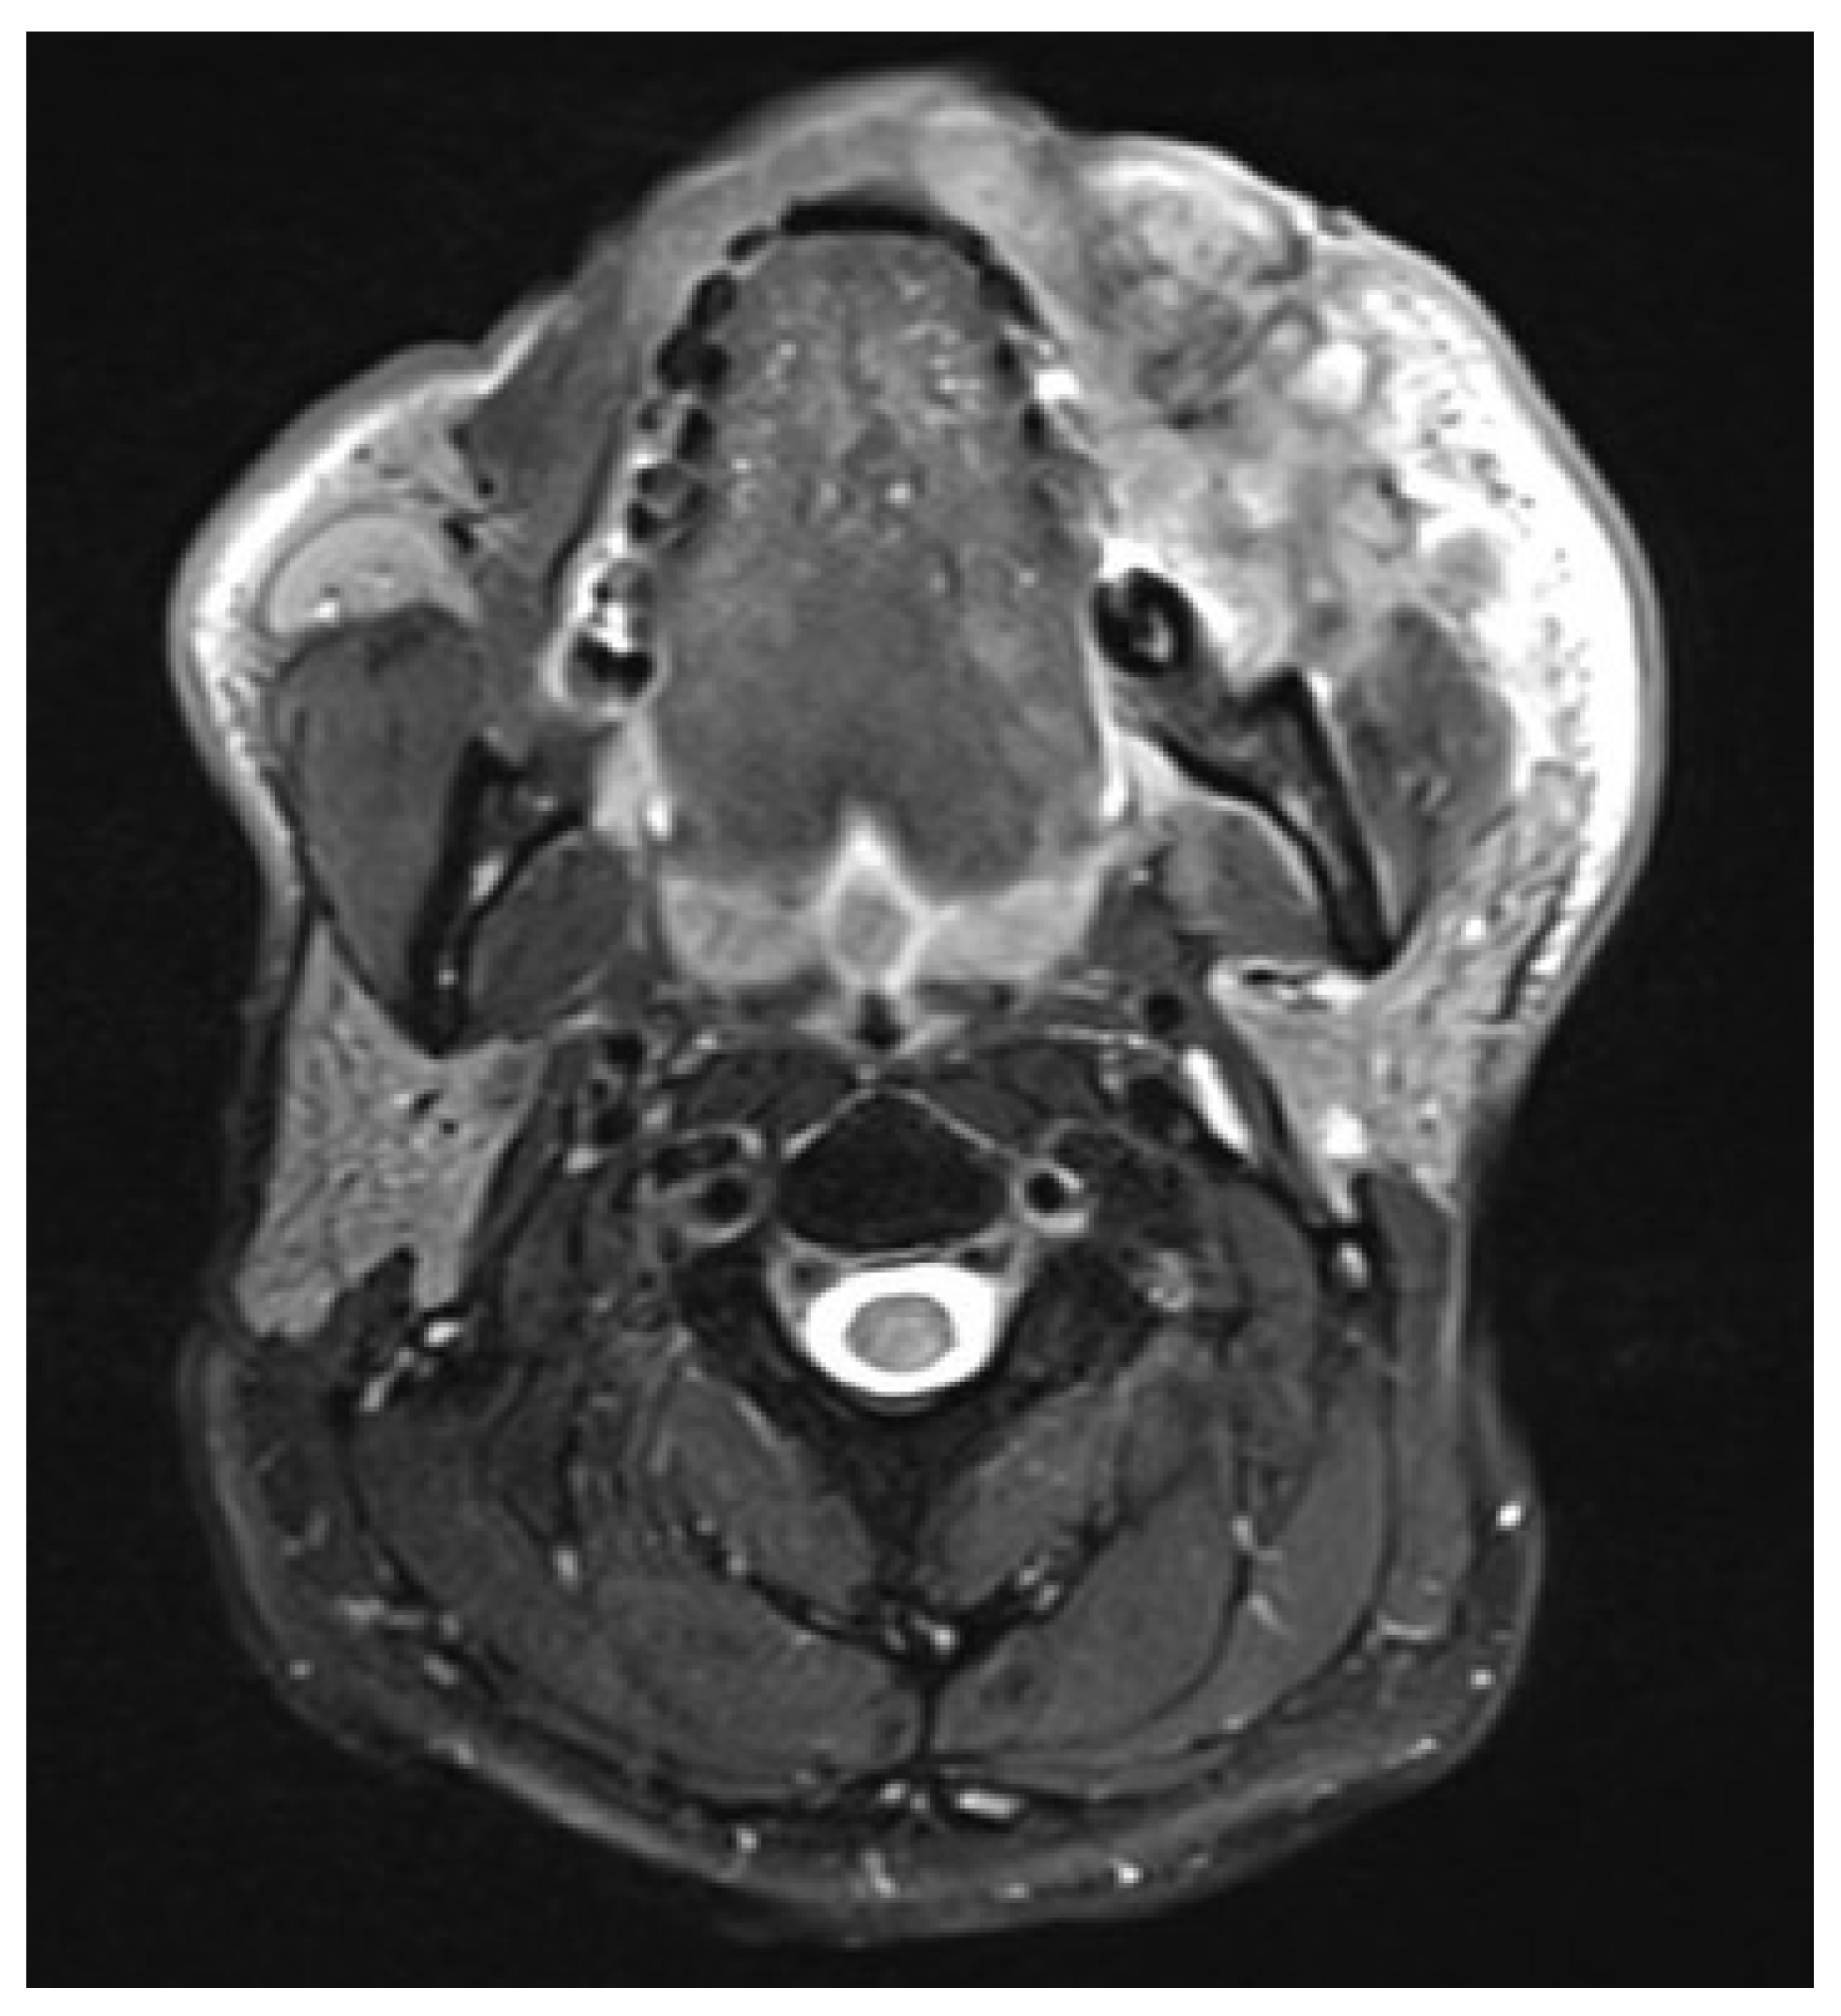

A 66-year-old male underwent subtotal mandibulectomy with bilateral neck dissections for a pT4aN0M0 moderately differentiated squamous cell carcinoma with free fibula osseoseptocutaneous flap reconstruction in February 2023.

The Aesculap Aeos robotic digital exoscope (Aesculap Inc., Lehigh County, PA, USA) was used during microvascular anastomoses providing excellent depth perception and ergonomics as well as allowing simultaneous visualization for assistants, operating room staff and trainees (Figure 1, Figure 2 and Figure 3). The exoscopic setup also permitted a more neutral working posture during the microsurgical phase.

Figure 1. Case 1—Preoperative MRI. Yellow arrows and circle indicate the primary tumor extension.